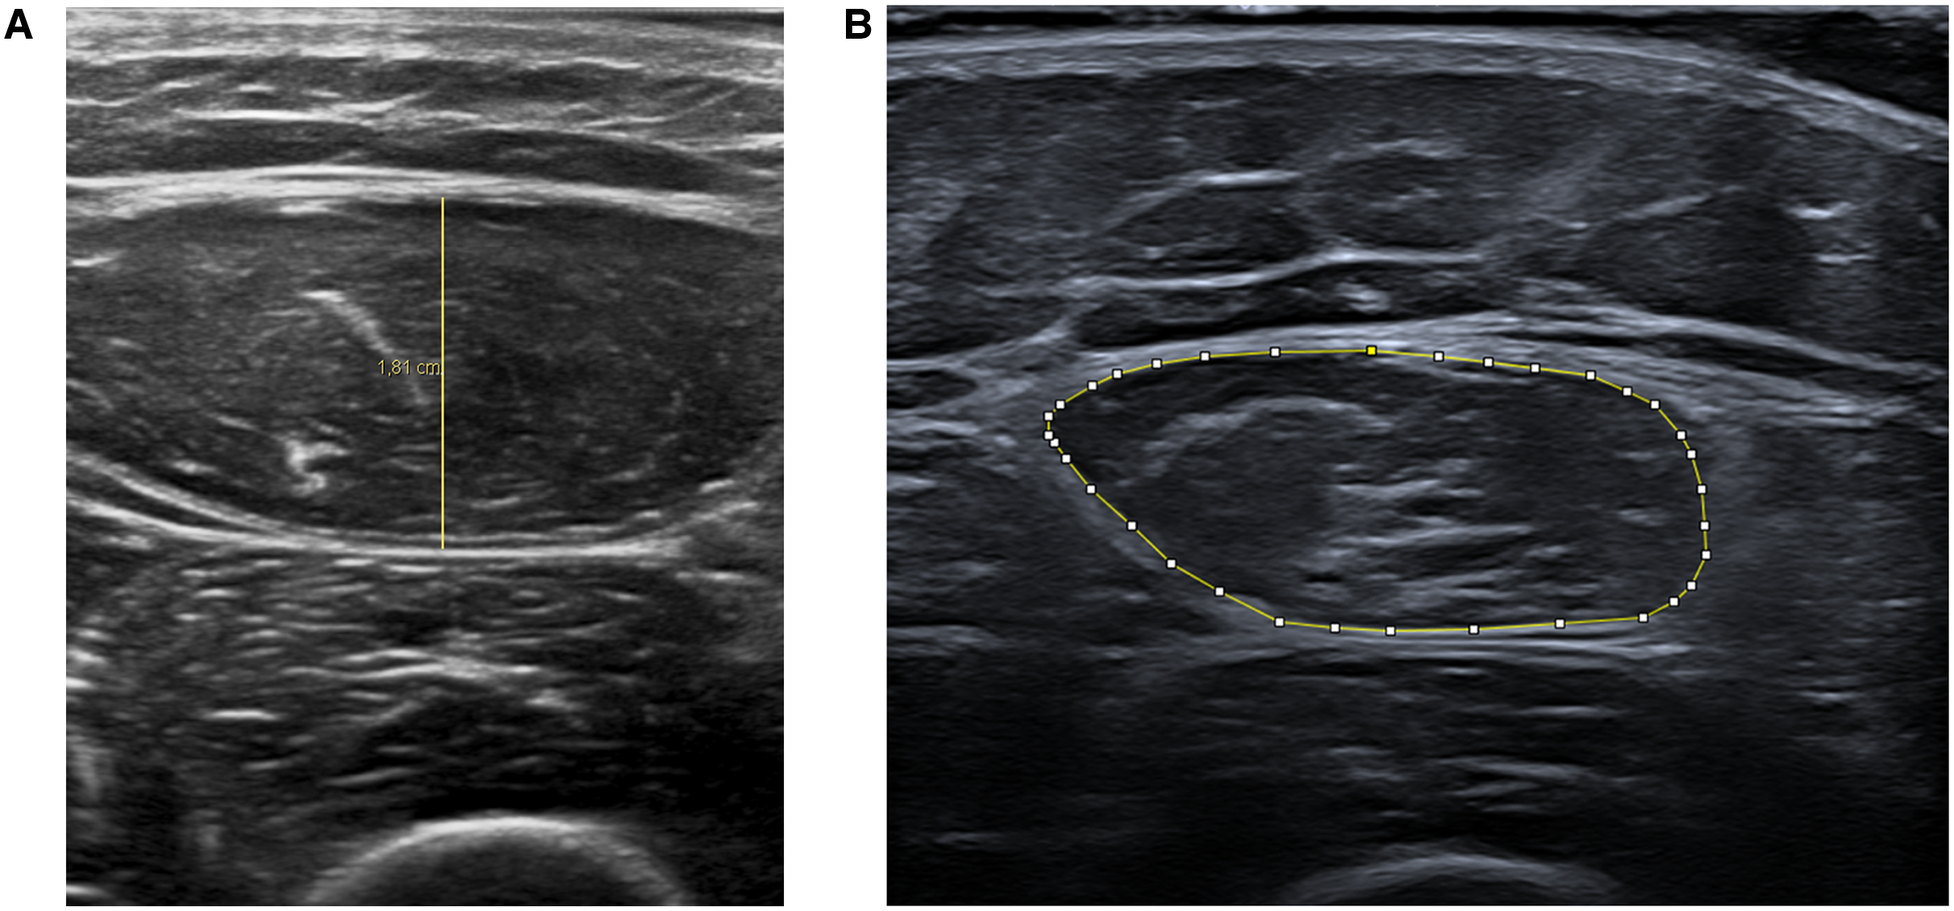

Muscle atrophy was evaluated using ultrasound measurements of the rectus femoris. Assessments were conducted twice weekly for the initial 4 weeks, followed by evaluations at 2 months and between 6 months to 1 year post-injury. Ultrasound measurements of muscle thickness and cross-sectional area provide reliable indicators of muscle wasting and strength loss (39, 40). The protocol for these measurements was adapted from the methodology described by Parry et al. (39).

The cross-sectional area of the rectus femoris was measured at two-thirds of the line joining the anterosuperior iliac spine and the upper edge of the patella. Three images were taken, and the measurements were averaged to obtain the area measurement.

Muscle thickness measurements (in centimeters) were performed using Philips DICOM Viewer R3.0-SP15 software. Area measurements (in square centimeters) were made using ImageJ software (Figure 2).

Figure 2

Representative ultrasound images showing rectus femoris muscle thickness (A) and cross-sectional area (B) measurements.